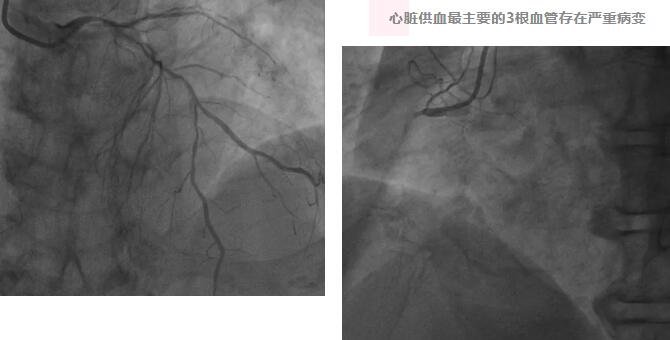

心内科手术团队制定了详细的手术方案和应急预案,确保在手术过程中能够迅速应对各种可能出现的情况。果不其然,经冠脉造影检查发现,刘大爷心脏供血最主要的3根血管均存在严重病变,左主干、左前降支和左回旋支重度狭窄,优势右冠发生急性闭塞,病情极其凶险,属高危的急性心梗。